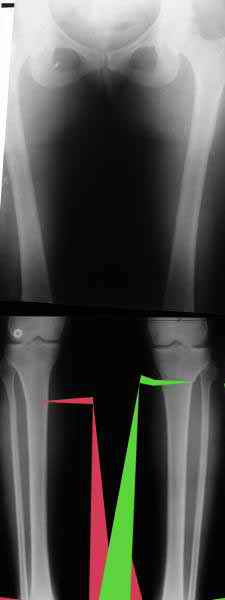

Отправитель: T. Derek V. Cooke 13 Сентябрь 2005, 23:51

|

Hello Alex:

Thanks for the clinical photo.

Your patient appears to have "Insquinting Knees"?

I am attaching a word doc with a 'print screen' of the program in use, showing the images being viewed and analysed

. On the right leg you can see some of the tools (from the tool bar above) applied to demonstrate a mild mech-axis varus of about 5 degrees.

On the left the bone landmarks used in the anlaysis are shown.

The data for the analysis are in the XLs sheet below, exported from the program automatically.

I have given a label of the abreviations and some normative values.

In essence she has a mild mech-axis varus of 7 degrees with some contribution from the femur (2) degrees and more from the tibia (6 degrees), none from the joint.

The analysis took about 6 mins.

Regards

Derek